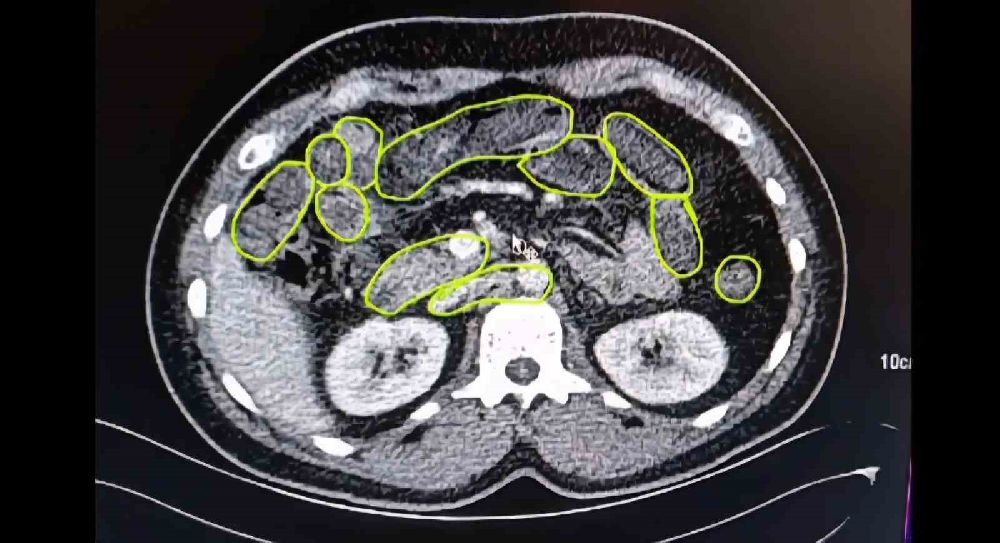

Şüphelilerin Kayseri Şehir Hastanesinde iç beden muayenesine alınırken, mide ve bağırsaklarında da çok miktarda kapsül şeklinde uyuşturucu olduğu değerlendirilen yabancı maddeler tespit edildi.